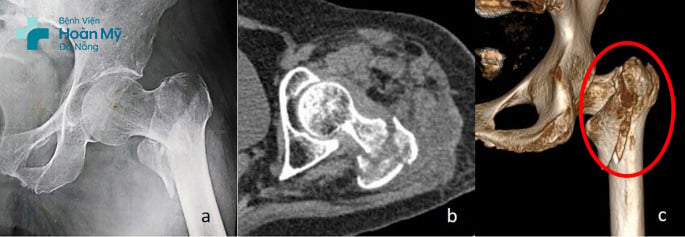

Người bệnh ngoại quốc H.A (60 tuổi) đến Bệnh viện Hoàn Mỹ Đà Nẵng do sưng đau nhiều khớp háng bên trái. Khai thác tiền sử, được biết cách thời điểm thăm khám 1 ngày, người bệnh bị ngã xe. Sau tai nạn, người bệnh bắt đầu đau và hạn chế vận động háng trái. Tại bệnh viện Hoàn Mỹ Đà Nẵng, người bệnh được chụp X-Quang, CT scan chẩn đoán và xác định bị gãy liên mấu chuyển xương đùi trái.

Hình ảnh gãy liên mấu chuyển xương đùi trái phức tạp trước phẫu thuật của người bệnh